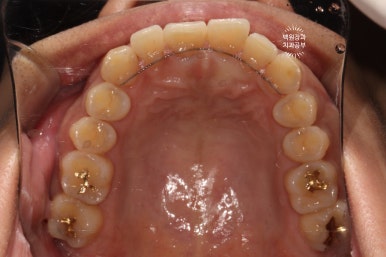

치료를 완료한 모습입니다.

사실 치료 결과는 '당연히?' 완벽해야되겠지만.. 이번 환자분에 있어서 치료 포인트라고 하면, 변색된 레진은 다듬어서 최대한 유지했고 꼭 필요한 부위만 레진충전으로 완료했다는 것에 있겠네요.

가운데 위치한 대문니들은 새로이 레진충전 함으로써 이차우식을 제거하고 깔끔하게 치료해드렸습니다.

마치 숨은그림찾기 같지만.. ㅎㅎ 옆면 충치를 레진치료로 마무리 함으로써, 뒤에서 보아도 깔끔해진 모습을 볼 수 있습니다!!

잘 보시면, 교정치료 후 유지장치가 있다고 해도 치실을 사용하실 수 있는 것을 보실 수 있습니다.

생각보다 치실을 사용할 수 없다고 생각하는 경우도 대부분 사용 가능한 경우가 많아요~~

레진치료를 받더라도, 잘 유지하기 위해서 인접면 구강위생관리는 필수입니다!!